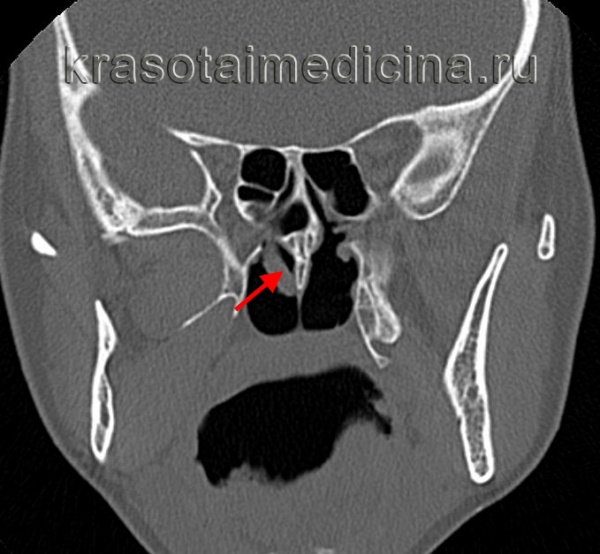

(Слева) При корональной «костной» КТ у девочки 14 лет с муковисцидозом (МВ) определяются типичные признаки ПНП, в т.ч. снижение пневматизации ячеек решетчатой кости справа за счет полиповидного материала, распространяющегося также в полость носа, и доброкачественное ремоделирование костей. Обратите внимание на большое мукоцеле решетчатой кости слева с распространением в орбиту и гипоплазию правой лобной пазухи.

(Справа)При аксиальной «костной» КТ у пациента с МВ визуализируется крупный полип в полости носа справа, связанный со средней носовой раковиной. Выраженная гипоплазия основных пазух часто наблюдается при МВ.